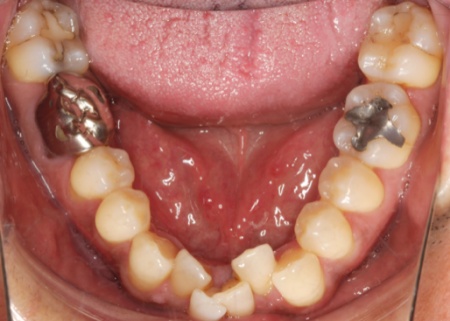

治療前

拝見したところ、上下前歯は歯が正常な位置からずれたりねじれたりしてデコボコに生えており、また前歯の噛み合わせが反対になる受け口も見られました。

このままの状態を放置すると見た目に悪影響が出るだけでなく、歯ブラシが当たりにくい部分に汚れが蓄積しやすくなり、虫歯や歯周病のリスクが高まります。

さらに、前歯が噛み合わないことが原因でほかの歯や顎に負担がかかり歯が割れたり、顎関節症を発症したりするおそれもあるため、矯正治療をする必要があると診断しました。

歯を正しい位置に並べるスペースを確保するために、下顎は左右の奥歯(第1小臼歯)を抜き、ワイヤー矯正とクローズドコイルを併用するスピード矯正を、上顎は抜歯せずにワイヤー矯正のみで治療する方法を提案し、同意いただきました。